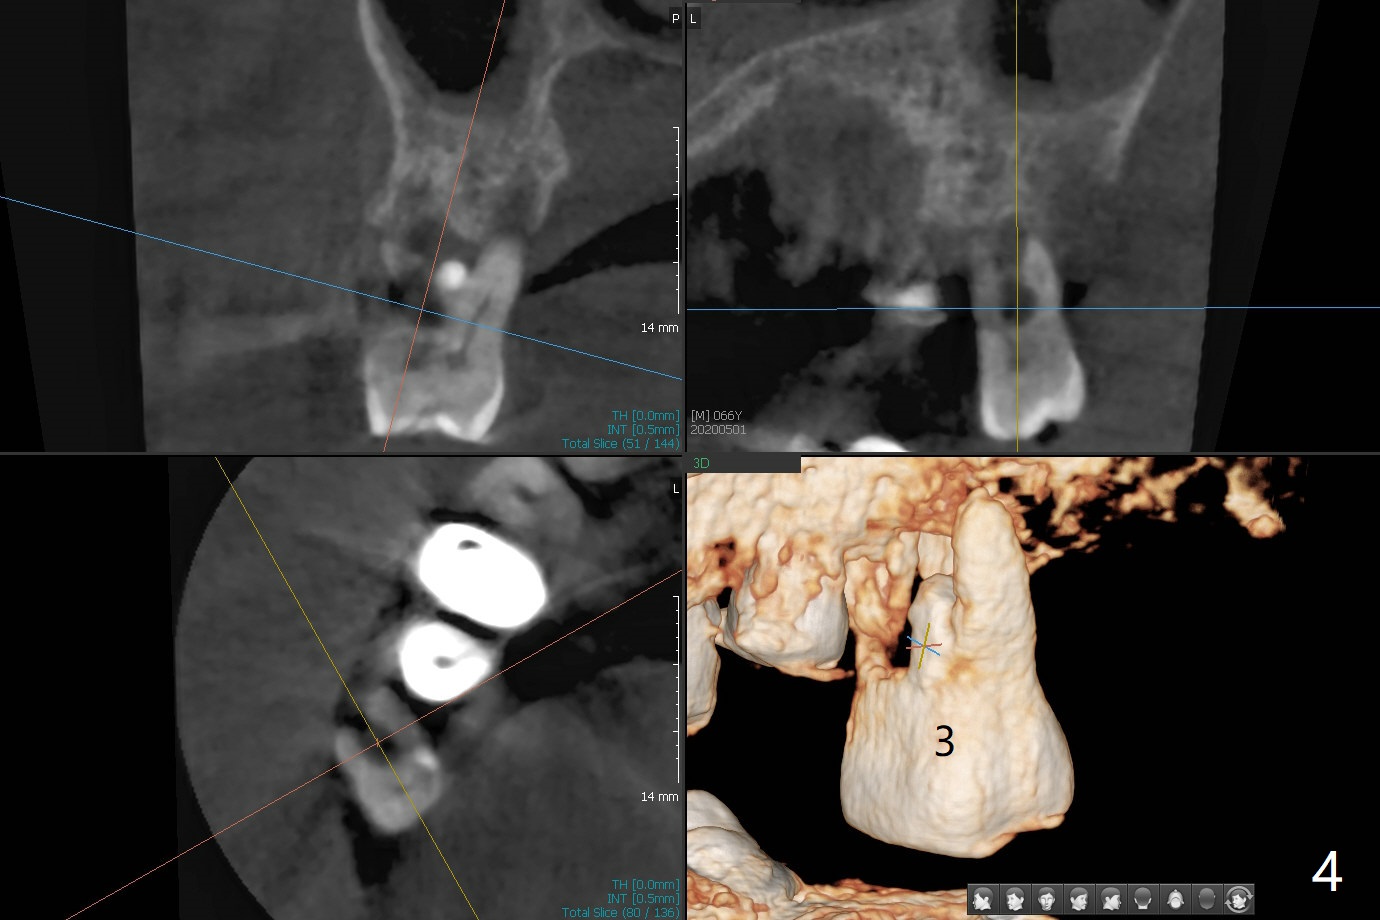

The patient returns for #4 extraction and immediate implant the 1st day clinic reopening after coronavirus lockdown. To reuse autogenous bone for #4 buccal gap closure, delayed implants are also placed at #13 and 14. It is much easier to determine the placement level of the immediate implant (open socket) with guide than that of the delayed ones (flapless) clinically. Immediate postop CT is taken for implant placement level confirmation (Fig.1-3). In fact the autogneous bone is too soft to be packed into #4 socket gaps. It has to be mixed with allograft to be packable. There is oozing when #14 healing abutment is placed. The hemorrhage is severe 4 days postop. The healing abutment is replaced by a healing screw. Hemostasis is achieved when the access is closed with GEM Cap and 4-0 Chromic gut suture. The patient will return for #3 extraction and socket preservation 1 month postop (Fig.4). To prevent postop hemorrhage, a cemented or temporary abutment will be placed at #4 before anesthesia, while .5 or 1.0 cc Augma bone will be placed at #3, covered with collagen plug and acrylic. In fact he cancels the appointment once because of symptom relief and will return 2 months postop. Sticky bone (Fig.5 *) and PRF is used at #3 for hemostasis, while a 5x5.7(3) mm pair (final) abutment is used to hold acrylic dressing in place. The latter remains in place with good oral hygiene 1 month postop (Fig.6 A: abutment). When the acrylic dressing is removed, the socket heals (Fig.7 K: the gingiva between the buccal and palatal sockets when the tooth was removed). The patient returns for impression 4.5 months postop. When the 5x5.7(3) mm abutment at #4 is reseated after cleaning, there is no horizontal gap between the abutment and implant in BW (Fig.8), while there is in PA (Fig.9). When a smaller abutment is seated (Fig.10), there appears to be a horizontal gap, whereas there is no vertical one. The situation is the same with #13 (Fig.11,12). The common denominator is 3.5 mm implant. With suspicion, BW is taken for the implant at #4 immediately before cementation (Fig.13). It appears that the abutment is most likely seated completely. There is no bone loss or screw loosening 4 months post cementation (Fig.14,15). One month later the patient agrees to have 3 lower implants to replace RPD.